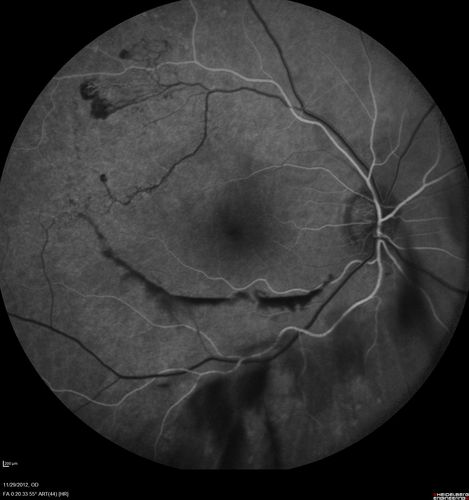

Branch Retinal Vein Occlusion with NVE (Neovascularization Elsewhere)

BRVO with Neovascularization and Vitreous Hemorrhage